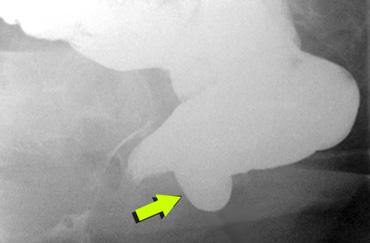

TRÁI: Nghi ngờ bệnh lý do khoảng cách lớn giữa trực tràng và âm đạo. Bệnh nhân chưa được uống thuốc cản quang. PHẢI: Sau khi uống thuốc cản quang barium dạng lỏng, quan sát thấy một thoát vị ruột non vào túi cùng Douglas (enterocele) kích thước lớn.

Hai giờ trước khi thực hiện thủ thuật, bệnh nhân uống 135 ml thuốc cản quang barium dạng lỏng để làm hiện ảnh ruột non (hình).